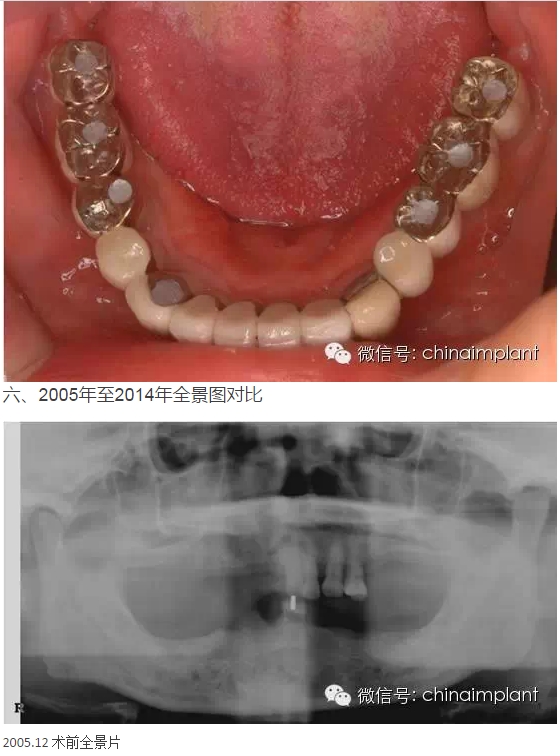

本案例已經(jīng)將近10年了(2005年12月),但是修復(fù)效果個(gè)人認(rèn)為很不錯(cuò),所以拿出來和大家分享。

從修復(fù)全景片上看到牙齒排列非常好

轉(zhuǎn):北京北一